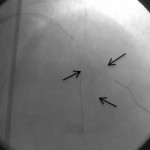

LAD damarı orta kısmına uzun, yan damar ağzına kısa stent çatal şeklinde yerleştirilerek kompleks darlık açıldı.